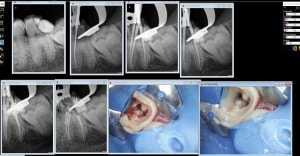

zoom_1570258573_suxrtb.jpg

zoom_1570258527_nvj0tg.jpg

zoom_1570258095_wh88wn.jpg

5A1ED2F3-46A0-45CF-8A09-ED06780C966D_dy9y3z.jpg

B4FABAC8-3F0A-44D1-A45E-D18E22A95ACB_zudxel.jpg